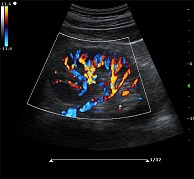

? ?● 彩色多普勒增強(qiáng)技術(shù)

? ? ? ?有效抑制彩色血流閃動(dòng)噪聲,提高血流分辨率和靈敏度

? ?● 多波束并行處理技術(shù)

? ? ? ?四倍波束并行處理,保證圖像良好分辨率的同時(shí),提高圖像刷新幀率